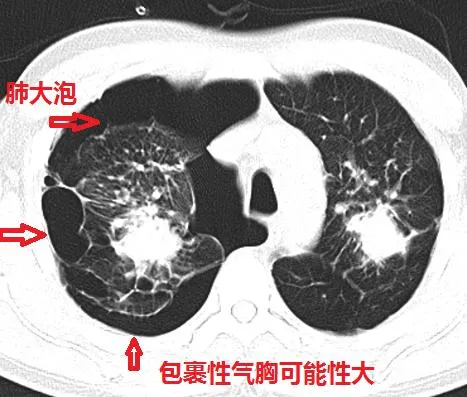

肺大泡患者需注意的几点

肺大泡是一种不可逆的肺部病损,患者需要特别注意日常生活的方方面面,以预防肺大泡破裂并改善肺功能。以下几点是肺大泡患者尤其需要注意的:

定期进行胸部X线检查是诊断肺大泡的重要方法。通过定期体检,可以及时发现肺大泡的变化,采取相应的治疗措施。对于体积较大、占据一侧胸腔70%~100%的肺大泡,手术切除可能是一个有效的治疗选择。